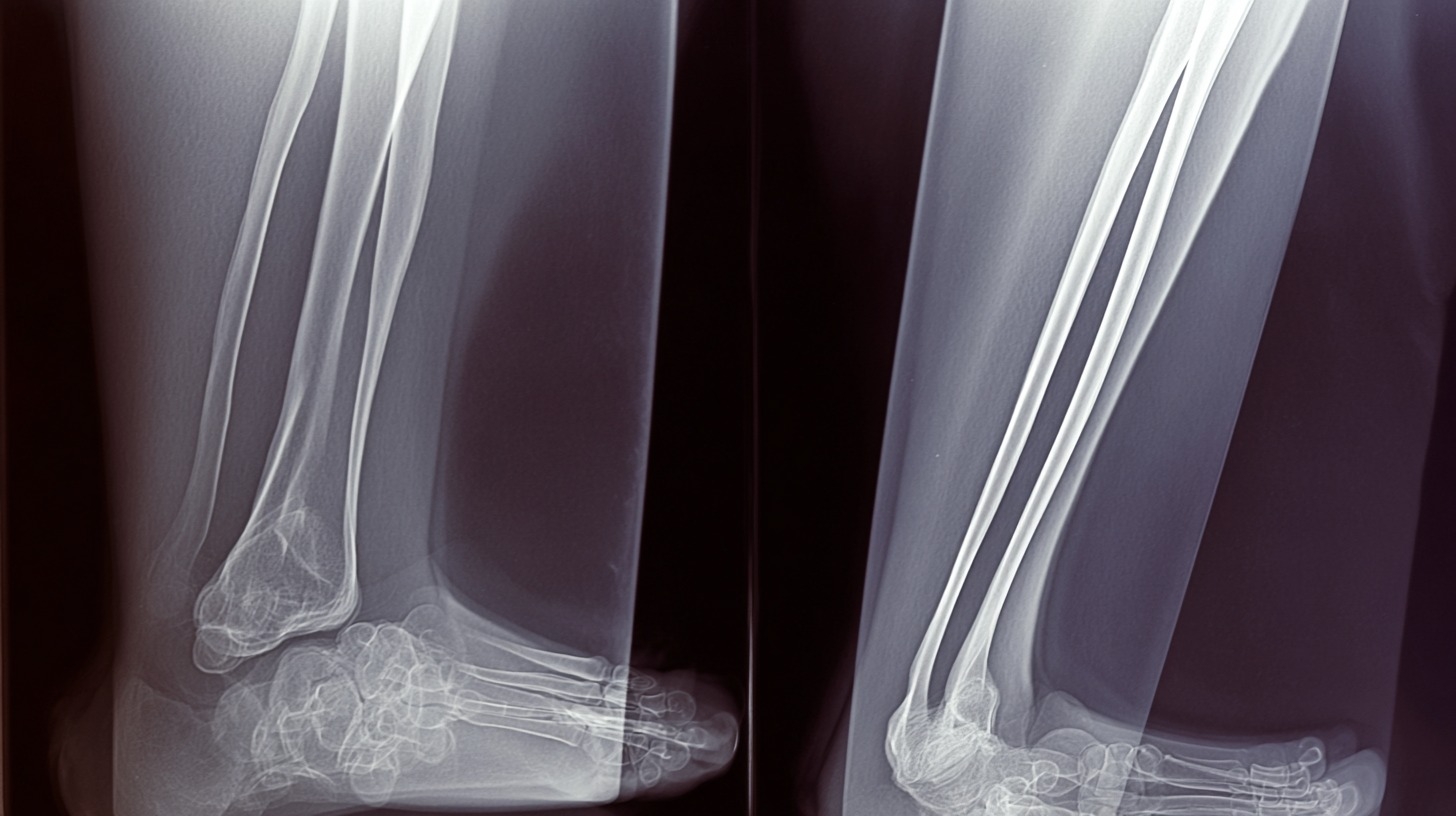

fracture 01

Le système ne connait ni la fatigue ni la baisse de vigilance. Il scrute les clichés radiographiques à la recherche de fractures, d'épanchements ou de luxations avec une constance quasi chirurgicale. En Irlande du Nord, ce dispositif permet déjà de réduire de manière significative le taux de lésions manquées, un problème récurrent dans les services surchargés.

Pour le patient, cela signifie un traitement immédiat et adapté, sans avoir à être rappelé deux jours plus tard parce qu'un radiologue a repéré une anomalie a posteriori. C'est un filet de sécurité numérique qui devient rapidement indispensable.